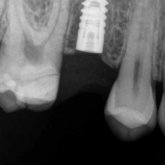

He received his Diploma in Implantology in 2016 from the University of Pretoria, which he passed with Distinction. He is also a member of the International Team for Implantology (ITI), which is based in Switzerland and offers members access to the latest research and cutting-edge techniques.

Porcelain crowns and restorations made in one appointment.

We make it a priority to incorporate the latest in dental technology in everything we do at our practice. ...